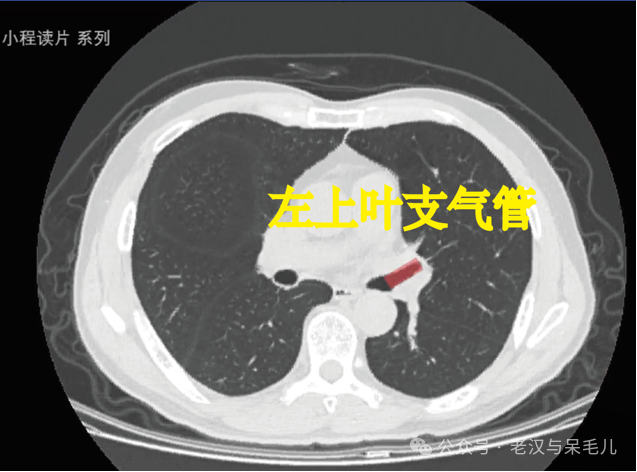

1.定位标志:左上叶支气管。

左主支气管向下延伸,发出左上叶支气管,左上叶支气管几乎呈水平行走,故在CT横断面上表现出平行管状形态。

图片

左上叶支气管迅速发出上支(相当于右上叶支气管)和下支(又叫舌叶支气管,相当于右中叶支气管)。

上支和下支行程较短,很快分为相应的肺段(上支分为尖后段、前段)。下支发出的上舌段更偏向于水平位,如果在CT上切更容易切出长条形,下舌段更偏向于垂直位,CT上切的话像是一个圆形。